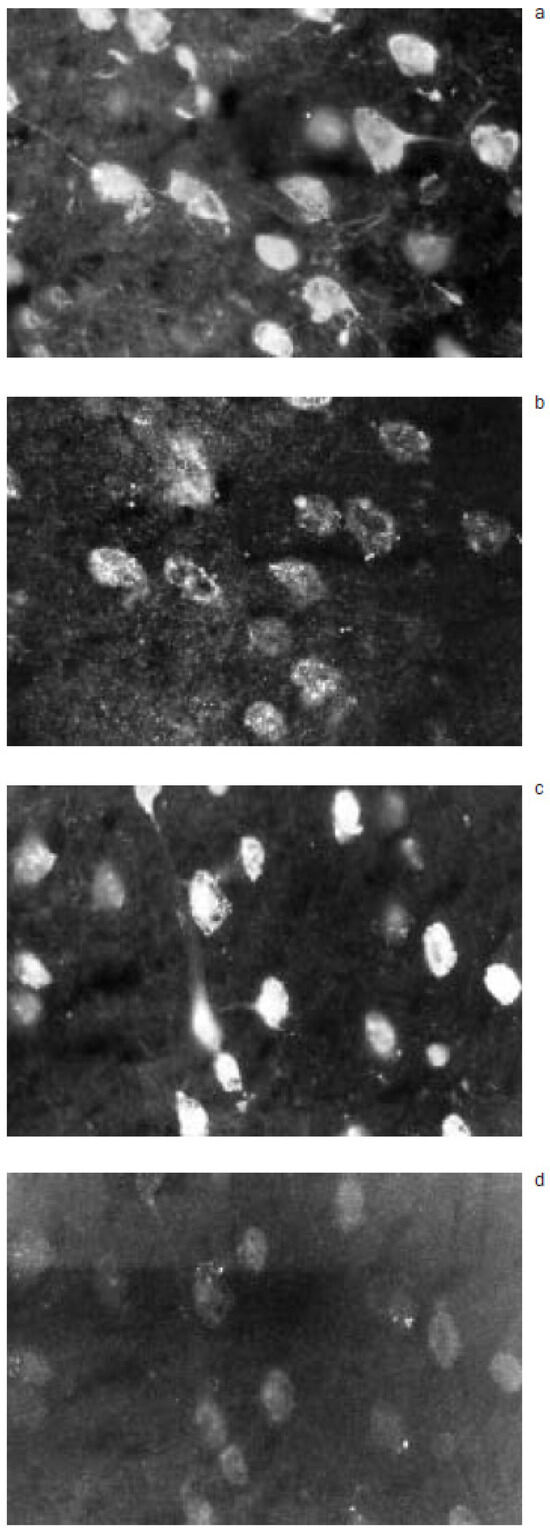

Amyotrophic lateral sclerosis Ig recognize CNS epitopes when passively transferred to mouse

by M. Schluep, B. Roth-Wicky and F. Regli

Swiss Arch. Neurol. Psychiatry Psychother. 1998, 149(4), 178-183; https://doi.org/10.4414/sanp.1998.01048 - 1 Jan 1998

Pathogenesis of amyotrophic lateral sclerosis (ALS), a neurodegenerative disease, is unknown and several hypotheses are still under investigation. In order to test the occurrence of an autoimmune phenomenon in ALS (and in acquired lower motor neuron disease (LMND)), we (i) tested ALS/LMND sera [...] Read more.

Pathogenesis of amyotrophic lateral sclerosis (ALS), a neurodegenerative disease, is unknown and several hypotheses are still under investigation. In order to test the occurrence of an autoimmune phenomenon in ALS (and in acquired lower motor neuron disease (LMND)), we (i) tested ALS/LMND sera on mouse central nervous system tissue sections, and (ii) passively immunized mice with ALS/LMND immunoglobulins (Ig). In in vitro and passive transfer studies, ALS/ LMND Ig (but not control Ig) labelled both neurons and astrocytes in the brain, brainstem, spinal cord and cerebellum of mice. These results emphasize the potential contribution of ALS/ LMND Ig to neuronal death process, and the role that astrocytes, that have the capacity to take part actively to immune responses, may play in this disorder Full article